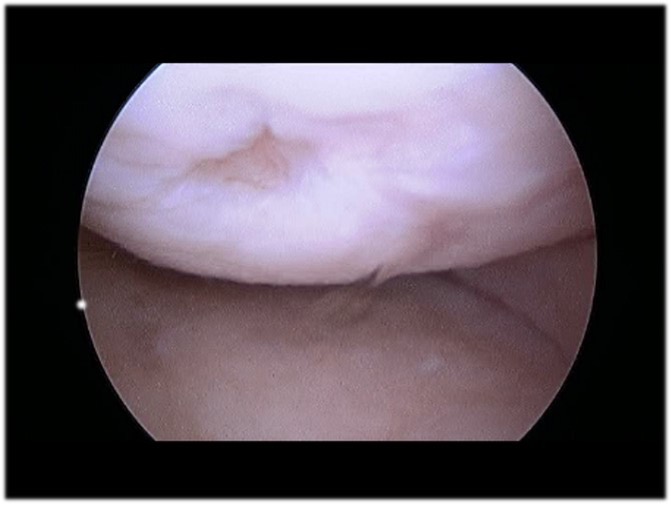

Articular Cartilage Injury Knee Cartilage Damage Shear Injury Orthopedic Knee Specialist Knee Cartilage Build Up When you have no cartilage in your knee, simple movements can be painful. The bones that meet at synovial. Cartilage is a tough, flexible connective tissue, that reduces friction between joints, holds bones together, and helps support weight. Articular cartilage is a complex and specialized tissue that provides a slick and bouncy cushion between bones at the joints. When cartilage. Knee Cartilage Build Up.

Articular Cartilage Defects of Knee Knee & Sports Orthobullets Knee Cartilage Build Up Cartilage is a tough, flexible connective tissue, that reduces friction between joints, holds bones together, and helps support weight. Synovial joints include the knee, elbow, hip, ankle, and wrist. When this cartilage is damaged by trauma, disease or. The bones that meet at synovial. When cartilage is damaged, people can. Cartilage—a type of connective tissue that lines the end of. Knee Cartilage Build Up.